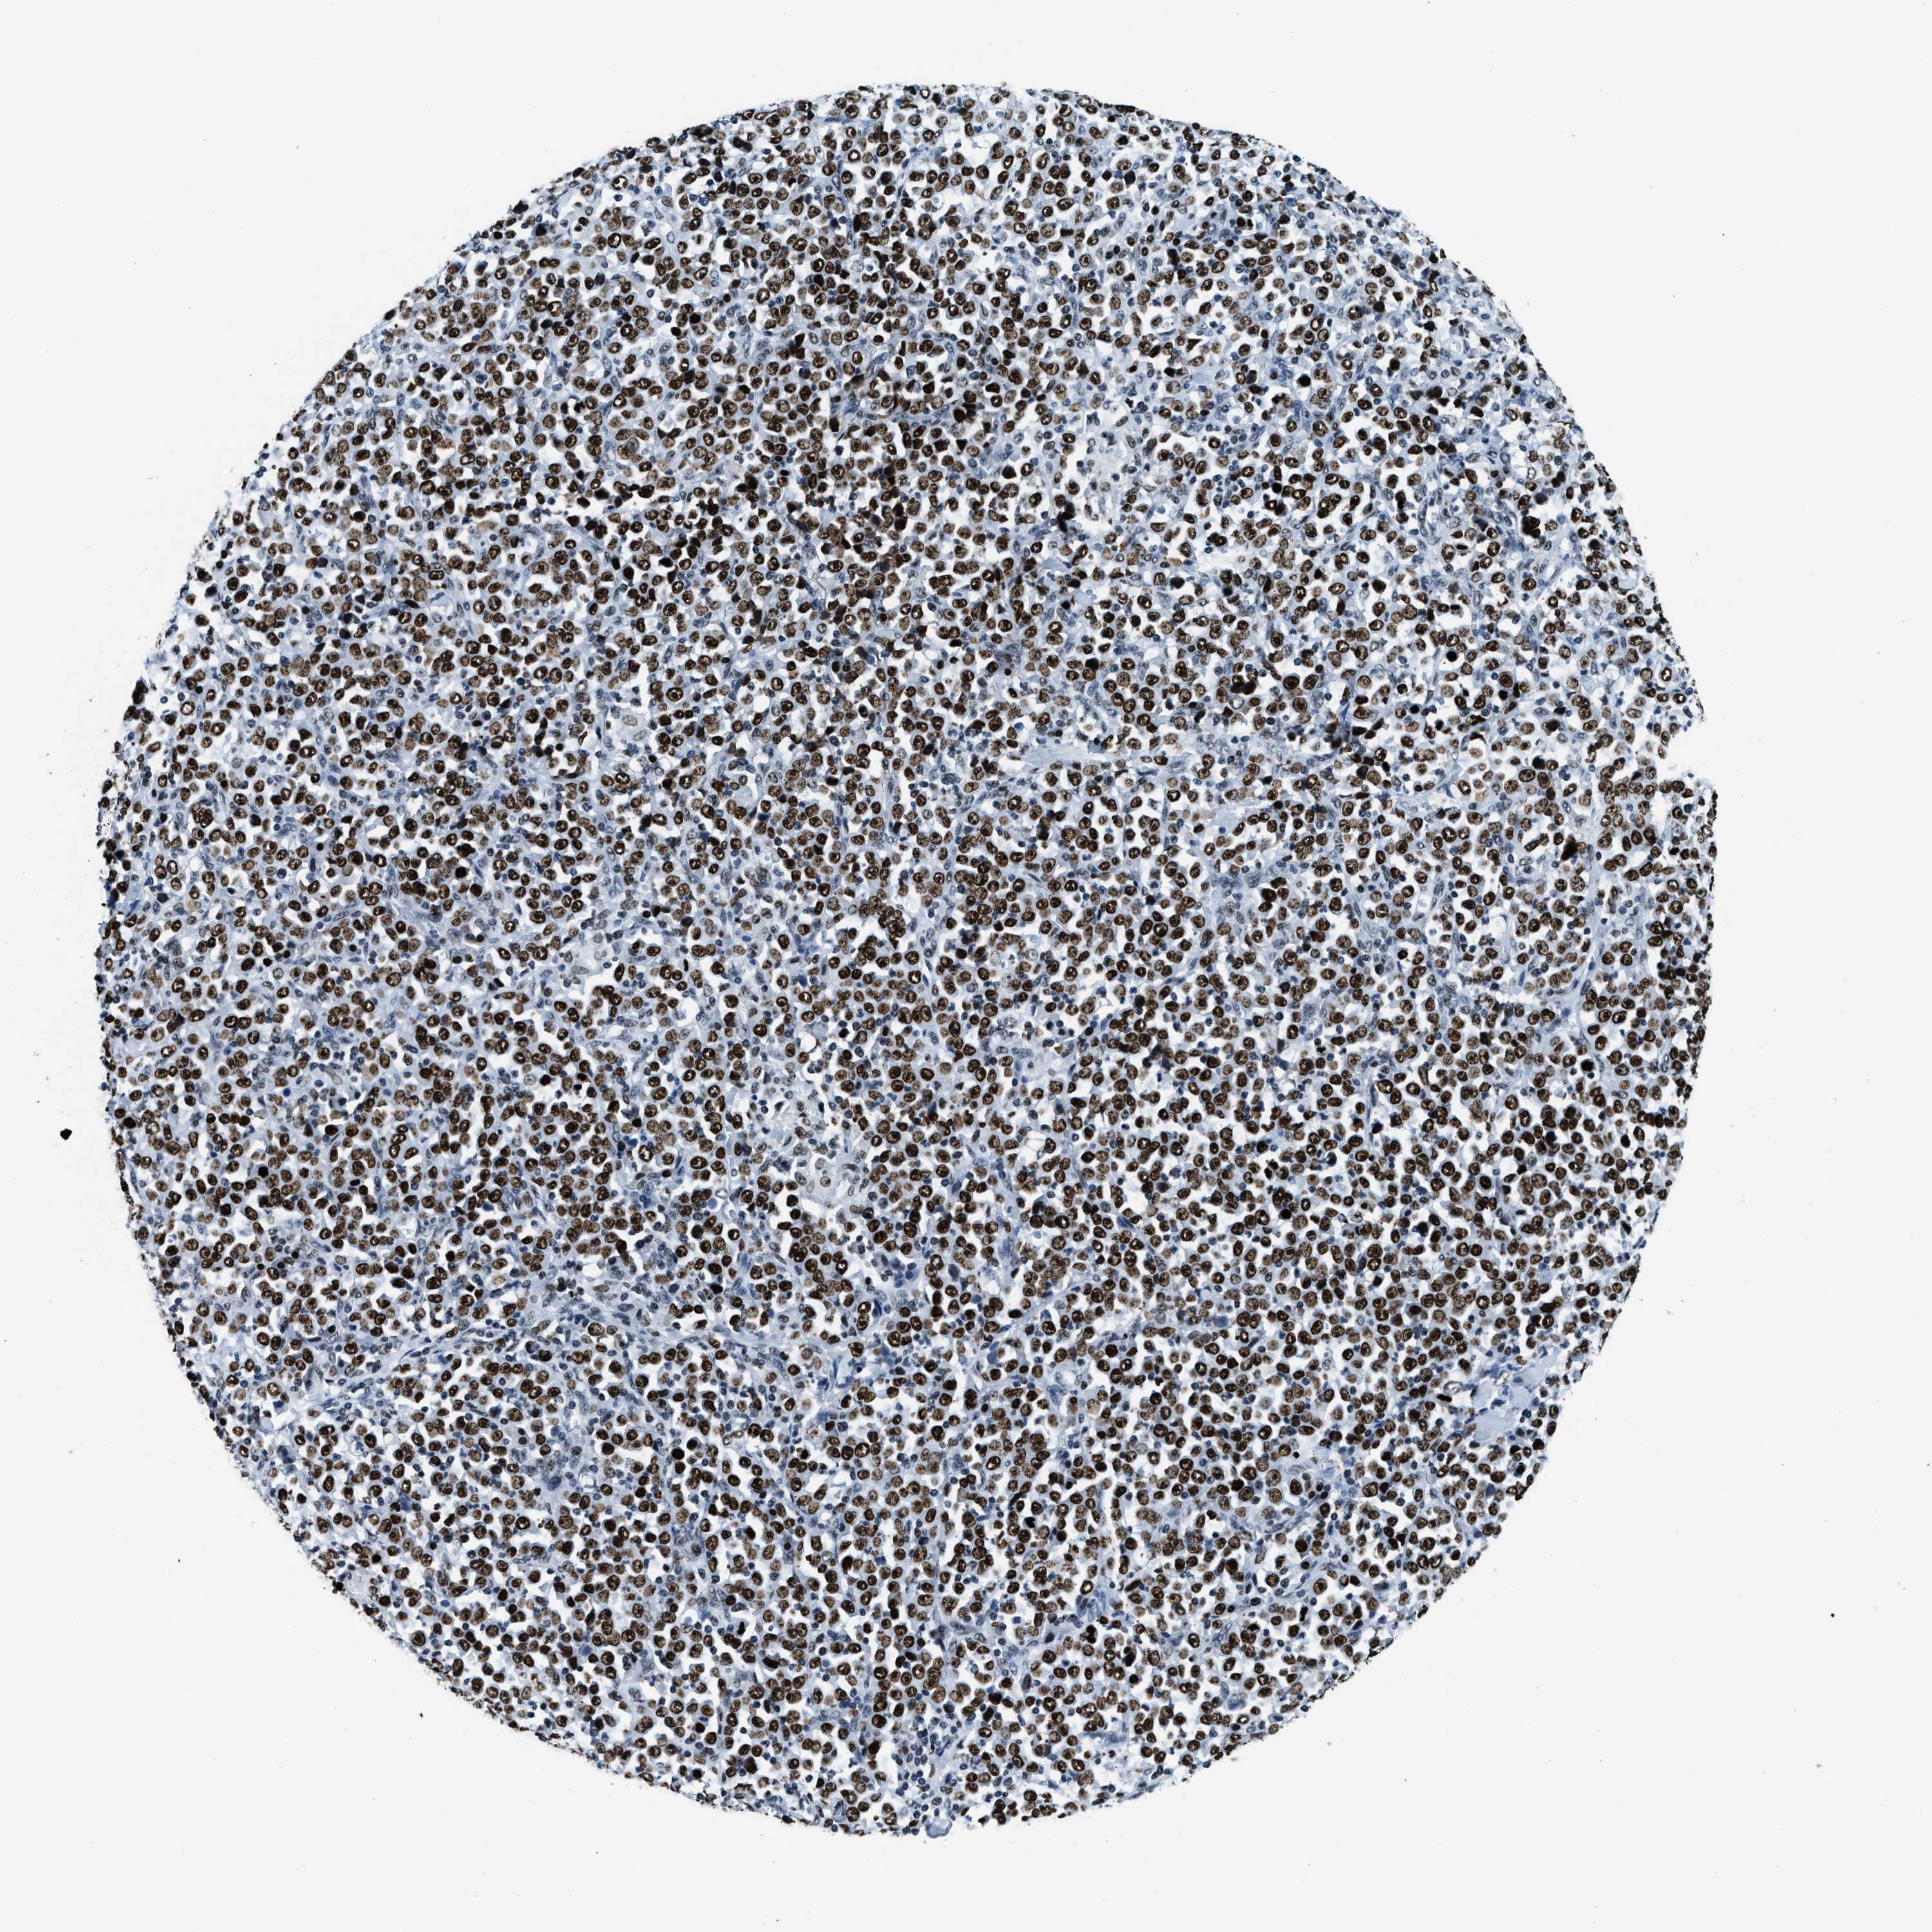

STOMACH CANCER - Protein expressioni

A mouse-over function shows sample information and annotation data. Click on an image to view it in a full screen mode. Samples can be filtered based on level of antibody staining by selecting one or several of the following categories: high, medium, low and not detected. The assay and annotation is described here.

Antibody stainingi

Antibody staining in the annotated cell types in the current human tissue is reported as not detected, low, medium, or high, based on conventional immunohistochemistry profiling in selected tissues. This score is based on the combination of the staining intensity and fraction of stained cells.

Each image is clickable and will lead to virtual microscopy that enables deeper exploration of all samples and also displays staining intensity scores, fraction scores and subcellular localization as well as patient and tissue information for each sample.

Antibody HPA019039

Antibody CAB009058

Staining

High

Medium

Low

Not detected

Intensity

Strong

Moderate

Weak

Negative

Quantity

>75%

75%-25%

<25%

None

Location

Nuclear

Cytoplasmic/membranous

Cytoplasmic/membranous,nuclear

Adenocarcinoma, NOS